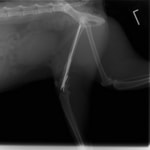

他院にて左大腿骨遠位の成長板骨折(salter-harrisⅠ型)が認められており、治療相談を目的として来院。当院にて、キルシュナーワイヤーを用いたピンニングにより骨折部位の整復を行いました。術後の経過は良好で、現在も経過観察中です。

術後レントゲン

機器

Arthrex社のターゲティングデバイスを用いてピンニングの位置を調整することで、確実な固定を行っています。当院ではこの手術器具以外にも、人の手術にも使用される様々な器具を導入し、手術精度を高め、また医療メーカーと新しい器具の開発、試作にも取り組んでおります。